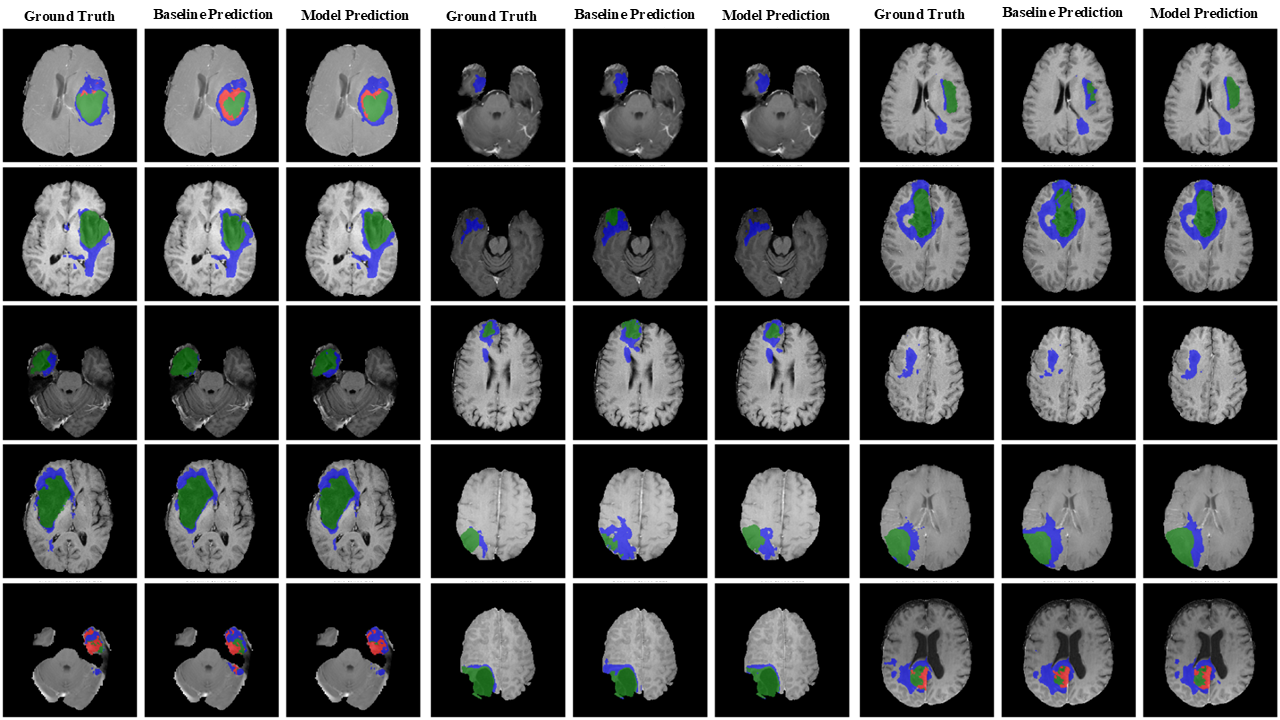

Refer to caption

Figure 6: Qualitative visualization of segmentation results produced by mmFormer on the Pretreat-MetsToBrain-Masks dataset. Model Prediction is mmFormer + fuzzy, Baseline Prediction is mmFormer.